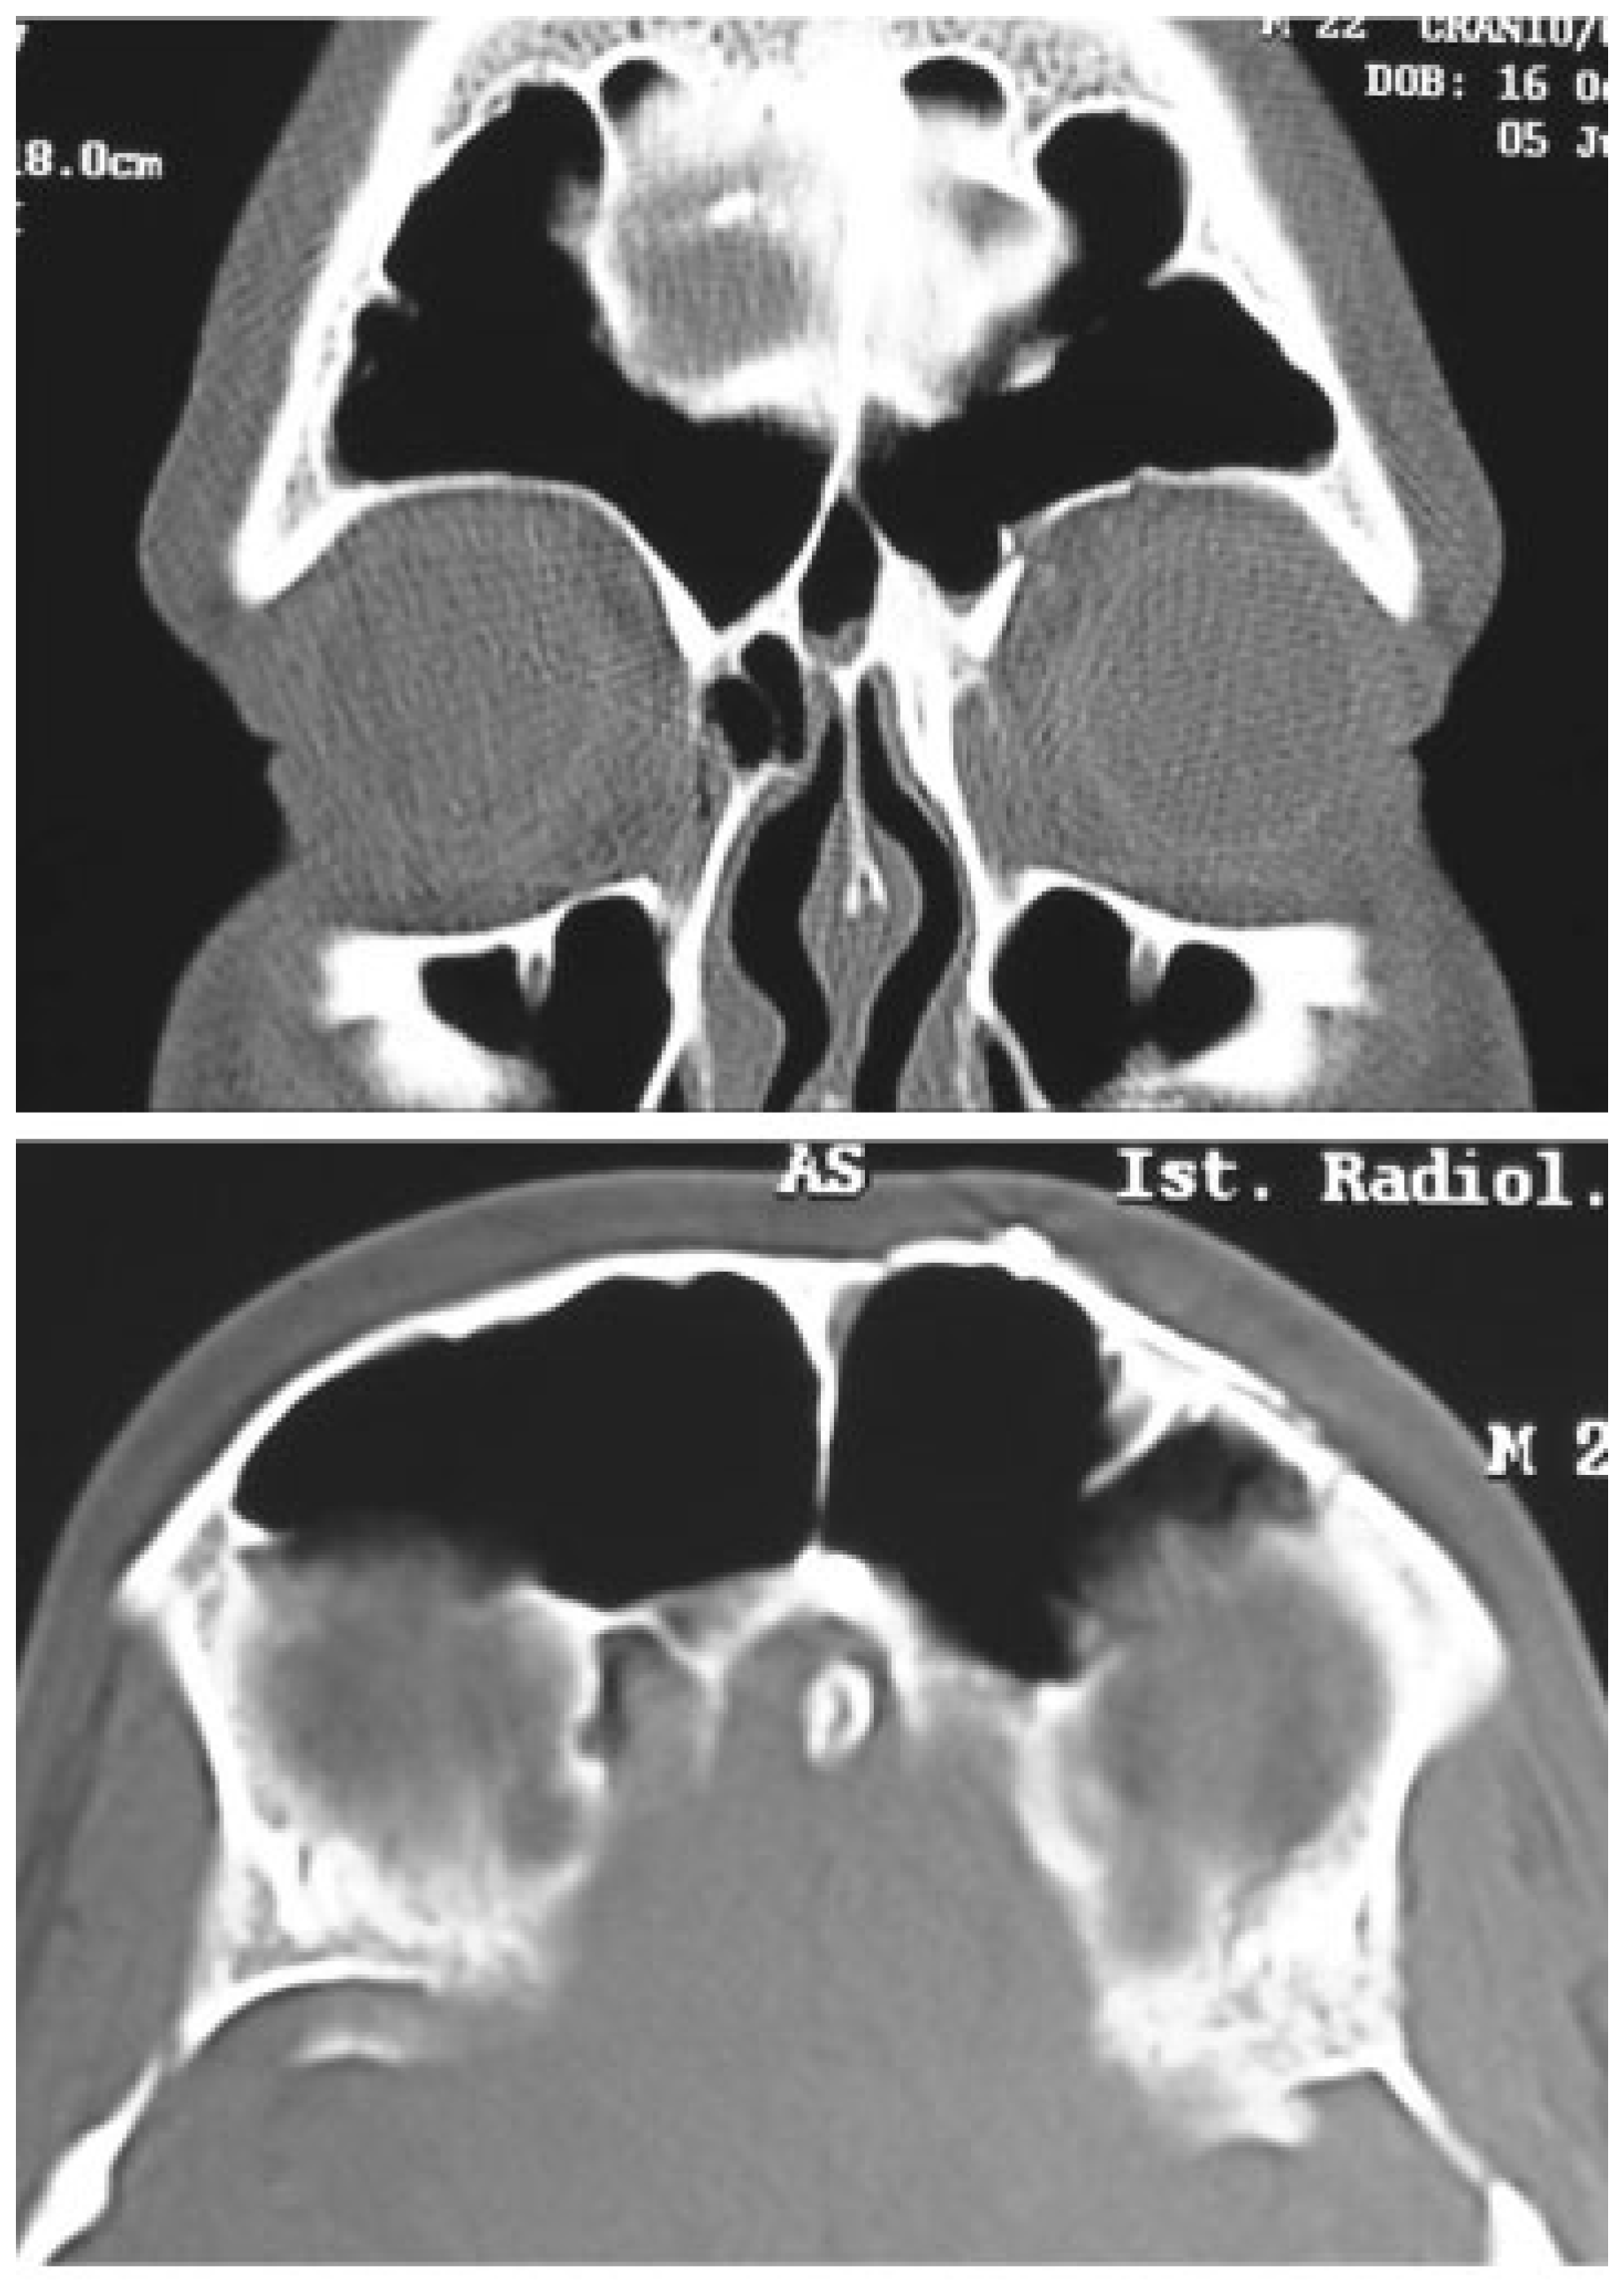

A 30-year-old man with male pattern baldness was referred to our department for a craniomaxillofacial trauma caused by a motorcycle accident. He presented left periorbital ecchymosis and edema, subconjunctival hemorrhage, eyelid ptosis, eyelid lacerations, enophthalmos, and pain during eye movements, along with diplopia (Figure 7). A CT scan showed displaced fracture of left frontal sinus anterior wall, nondisplaced fractures of frontal sinus posterior wall, and blowout fractures of the inferior, medial, and superior left orbital walls with dural laceration, needing combined neurosurgical and maxillofacial repairs (Figure 8). With a left unilateral zigzag pretrichial incision, we were able to widely expose the frontal sinus anterior wall fracture. Through a craniotomy, performed by a neurosurgeon, the damaged left orbital roof was reduced. The frontal sinus was then obliterated with abdominal fat and stabilized with microplates and screws (Figure 9). Finally, inferior and medial orbital walls were reconstructed with polyethylene implants (Medpor, Strykez Corporation, Newnan, Georgia) using a Lynch incision and a transconjunctival incision. A postoperative CT scan confirmed a correct surgical reduction (Figure 10). The pretrichial incision healed without aesthetic complications (Figure 11) and after 30 months of follow-up, the scar is insignificant (Figure 12).

Figure 8. Preoperative coronal and axial computed tomography images.